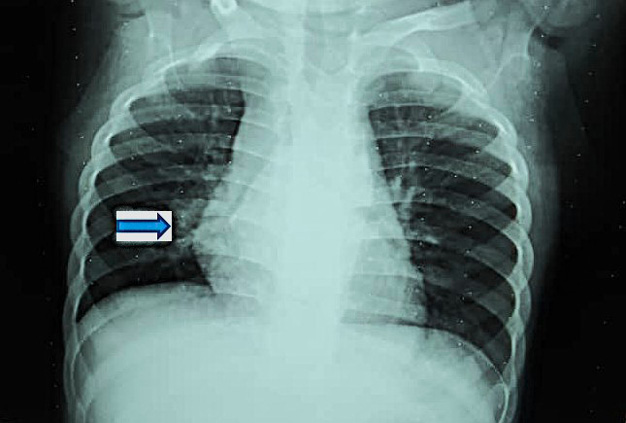

Imagen de radiopacidad, retrocardíaca.

Engrosamiento hiliar derecho e infracarinal (compatible adenopatías de complejo primario tuberculoso).

Paciente femenina de 1 año y medio, no VIH, nacida a término de 38,1 semanas de gestación sin problemas maternos o fetales, con un peso de 3.560 g, talla 51 cm, circunferencia cefálica de 34,5 cm. Parto eutócico, apgar 9/9, sin problemas perinatales y caída del cordón a los 6 días. Lactancia materna exclusiva (6 meses) y complementada hasta el año, con una alimentación balanceada y buena ganancia de peso. Al año de edad, pesaba 10,5 kg. Desarrollo psicomotor y del lenguaje acorde con su edad, camina desde los 12 meses. Niega ingresos, aunque ha tenido 2 episodios de rinofaringitis aguda de corta duración, antes del año de edad; no uso de antibióticos. Asintomática en el momento actual, padre exrecluso que se diagnosticó con TB pulmonar en el año 2024. En las acciones de pesquisa a los contactos, se estudia a la niña que resulta examen físico negativo, asintomática respiratoria, con buen progreso pondoestatural y buen estado nutricional. Peso actual de 12 kg con talla de 78 cm y con un examen físico negativo, sin ningún otro riesgo aparte de la corta edad y ser contacto estrecho de un paciente bacilífero. Vacunación completa para su edad, según normas de nuestro país. La prueba de tuberculina resulta hiperérgica, 18 mm, con presencia de ulceraciones. Se le realiza Rayos x de tórax antero posterior en el cual se sospecha adenopatía hiliar bilateral y subcarinal.

El Centro de Referencia de TB Infantil plantea un diagnóstico de TB pulmonar primaria subclínica y, ante la imposibilidad de obtener muestras respiratorias, se decide enviar la muestra de heces, como recomienda la OMS, al Laboratorio Nacional de Referencia en Tuberculosis del Instituto Pedro Kourí, para realizar el ensayo molecular Xpert® MTB/RIF Ultra; utilizando como método previo para el tratamiento de las heces el Sistema Simple de un Paso (SOS, KNCV TB Foundation, Hague, Netherlands).8 Se les explica a los padres en qué consiste el estudio, beneficios del mismo y se les pide su consentimiento para realizar la prueba, dando como resultado: MTB Detectado Trazas/ Resistencia a la Rifampicina Indeterminada. Se decide iniciar el tratamiento de primera línea para TB sensible a fármacos, según programa, con las cuatro drogas (isoniacida, rifampicina, pirazinamida y etambutol) en la primera fase (60 dosis, según peso de la paciente) y una segunda fase diaria acortada también de 60 dosis, por tratarse de un caso no severo.7 La medicación es bien tolerada, con buena ganancia de peso y resolución radiológica, por lo que termina con éxito el tratamiento. Se mantiene en seguimiento por consulta durante dos años, de acuerdo al protocolo vigente. Por la naturaleza paucibacilar de la TB en estas formas primarias y la rápida resolución radiológica, no se realiza toma de muestra para examen directo y cultivo del contenido gástrico en ayunas por ser un proceder invasivo, no aceptado por los padres. En estos momentos el padre también tiene alta epidemiológica con cultivos negativos.